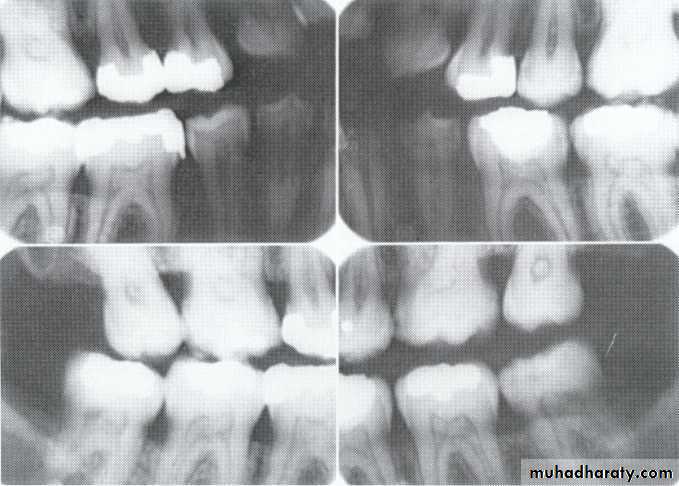

Radiographically:

Bulbous crownsCervical constriction

Thin roots

Early obliteration of roots canals & pulp chambers.

Radiographically (Type I& II ):

partial or total obliteration of pulp chambers & root canals by continued formation of dentin.

roots may be short & blunted.

Normal cementum, periodontal membrane & bone .